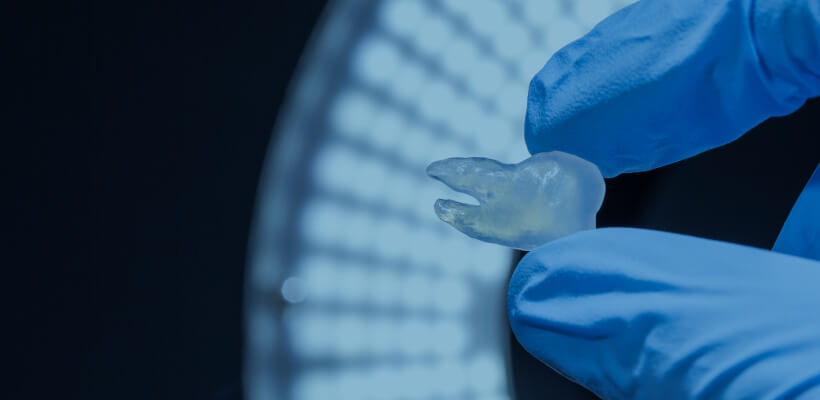

Preoperative simulation

Tooth transplant

Wisdom teeth for grafting can be simulated before the surgery.